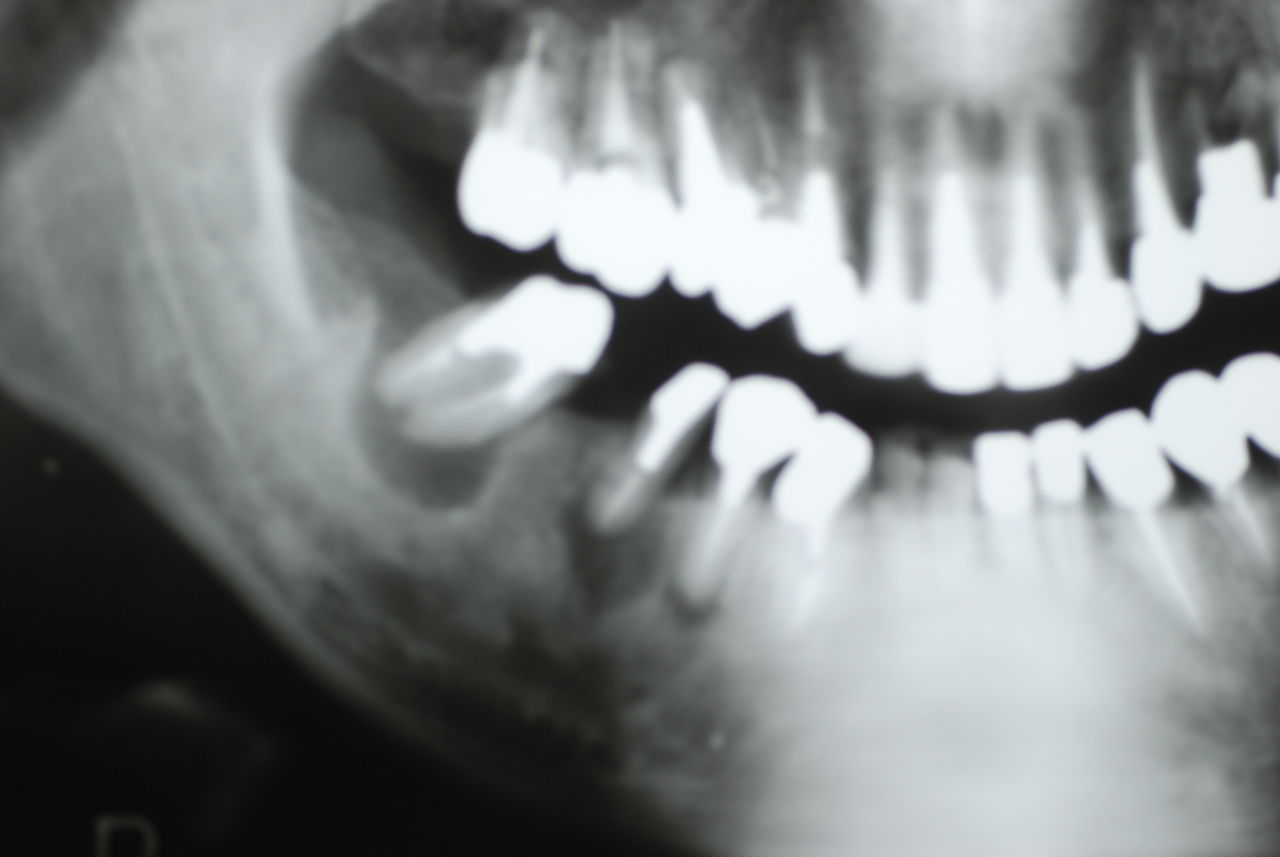

歯周病の疑いで東京のかなり遠方の方が来院されました。

驚くべきことですが、定期検診は受けていたそうです。しかしながら歯周病の指摘は受けたことがないそうです。

何故か?定期検診が虫歯のチェックのみになり、又肝心の歯周病の検査や歯周病の部分の予防や治療のためのブラシの使い方などを学んだ事がないのです。